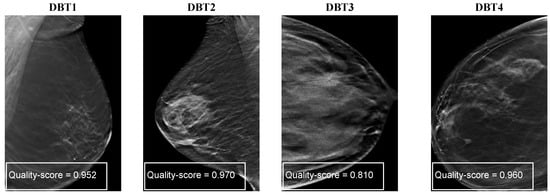

Figure 6 shows four examples of distorted DBT images. As we can see, they show the presence of DBT image artifacts such as darkness and brightness (DBT1, DBT2) generated by the gamma correction to mimic a potentially reduced radiation dose, speckle noise (DBT3), and blurring (DBT4). In Figure 6, we can observe that the SSIM and PSNR values respond differently for each noise type of the noisy DBT images.

Figure 6. Examples of distorted DBT images with the corresponding PSNR, SSIM, and corresponding quality scores.